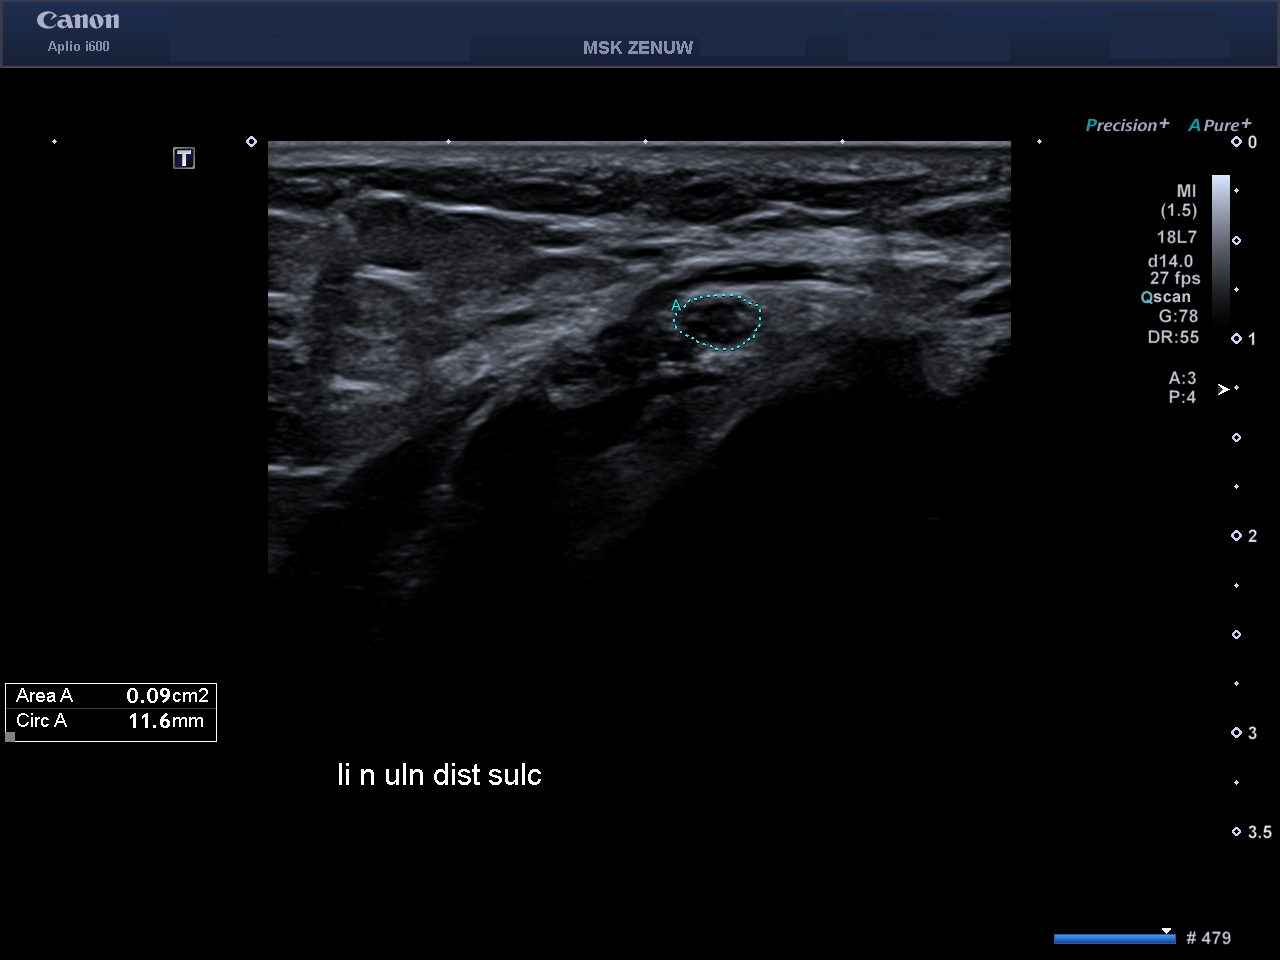

Представляємо вам клінічні випадки візуалізації періферійніх нервів на Aplio i800 з використанням високочастотного датчика 24 MHz. Ці приклади яскраво говорять самі за себе.